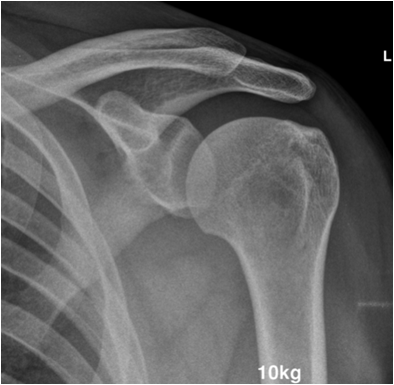

17.2.1.1. Stress films:

Joint relationships can frequently be evaluated better with the aid of stress films. Stress may be applied either by weight bearing (evaluation of the acromioclavicular joint) or by external stress applied to alter the at-rest relationship (evaluation of ankle ligaments). Stress films are used to test joint stability in suspected ligament injury. Images are taken under defined conditions with weight or pressure applied. Subluxation or joint space widening indicates partial or complete rupture of the ligaments tested. Before ordering stress images a set of conventional images in mandatory to exclude fracture.

Fig. 4. Stress test of acromiclavicular joint instability. The patient is holding 10 kg weight in each hand. Note the step in the right acromiclavicular joint indicating injury to the ACG capsule and the coracoclavicular ligament.